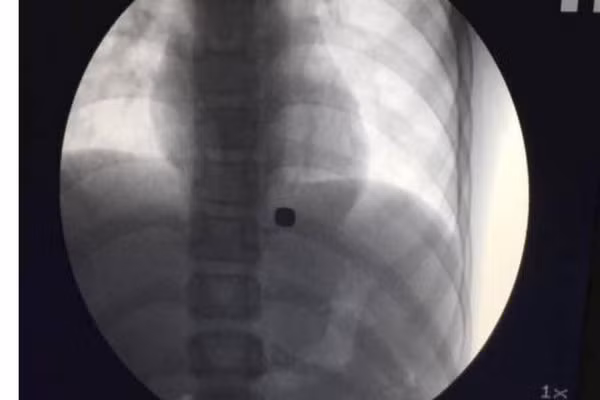

Nam châm có kích cỡ chỉ bằng chiếc cúc trong dạ dày cậu bé

Vì vậy, ông Hu Bing, Giám đốc Trung tâm nội soi dạ dày-ruột tại Bệnh viện Tây Trung Quốc ở Thành Đô, đã quyết định sử dụng phương pháp đặc biệt, đó là dùng một nam châm cực mạnh để loại bỏ 2 nam châm có kích cỡ chỉ bằng chiếc cúc ra dạ dày cậu bé.